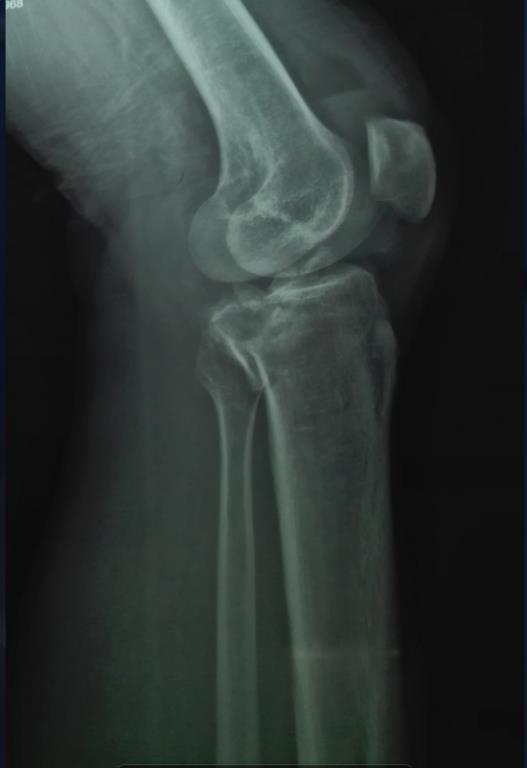

左膝盖骨折 问题已结束讨论

骑电动车摔伤,左膝盖肿胀,现在五个脚趾都还能动

你好!你有胫腓骨的骨折的情况,没有伤口属于闭合性骨折的情况,给予手术复位内固定手术,利于骨质的愈合及功能的恢复。膝关节里面有前后交叉韧带、半月板、内外侧副韧带是在膝关节腔里面的,不是在骨头的外面,要应用膝关节镜检查才能看见。<br />